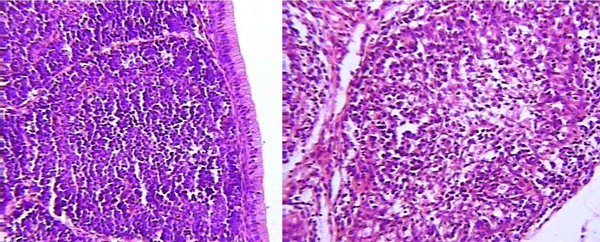

Imagen No 1. Folículo linfoide normal de un pollo de engorde de 31 días de edad (hematoxilina-Eosina, 40X)

Enfermedad de Gumboro: depleción linfoide y lesiones atróficas, pueden ser inducidas por las vacunas? - Image 2

Imagen No. 2 Bolsa de Fabricio de un pollito de engorde de 7 días de edad. A edades tan tempranas como a los 7 días, los cortes histológicos de bolsa de Fabricio muestran folículos no muy densamente poblados en relación con las imágenes de bolsas de aves de mayor edad, parecería como si estuvieran depléticos cuando en realidad no lo están. En la fotografía de la derecha se observan algunos "puntos negros" que podrían corresponder a linfocitos en proceso de picnosis. Este podría ser un efecto de virus vacunal ya que la replicación del virus de vacunas a virus vivo pueden producir este efecto